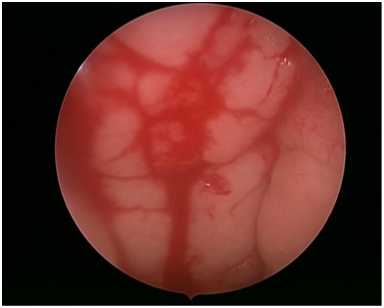

After admission and evaluation in a pediatric center & ruled out ulcer, maillary weises, the patient was referred to our ENT clinic for more evaluation. Full HEENT examination revealed normal. The main complaint was hematemesis. Detailed history revealed complaint of recurrent epistaxis 1-2times per month. Also, she had history of black colored stool but no change in urine. No significant family history of bleeding tendency. Under general anesthesia, nasal endoscopy done showing spontaneous nasopharyngeal bleeding (Figure 1) from the adenoid not controlled with suction cautery, then adenoidectomy done & hemostasis done by packing with xylomethazolin & observation for 7minutes then pack removed with no further bleeding. Patient extubated & shifted to the ICU 1 day for observation. Post operative, the patient became symptom-free and had no more complaint of bleeding or any other complication during our 12months follow up. Pathology of nasopharyngeal mass was reported to be non specific chronic inflammation .We believe that adenoid tissue was the source of the bleeding.

Figure 1 Nasal endoscopy shows spontaneous adenoid bleeding.